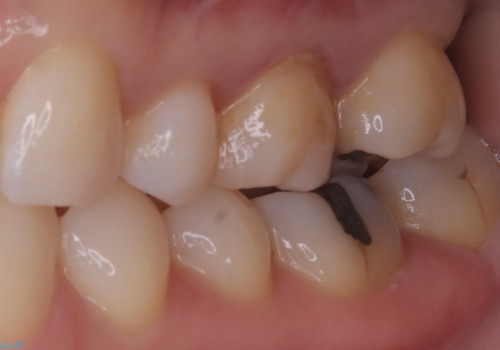

左上6番に入っている保険適応のメタルインレーと歯質との境目(近心側室エリア)に不適部位を認め、そのくぼみに汚れが停滞しやすい状態となっていました。

適合性・審美性を考慮し、セラミックインレーでのやり替えとなりました。